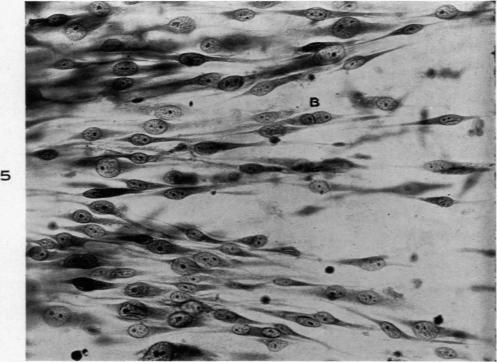

Characteristics of a Liposarcoma Grown in Vitro.

Am J Pathol. 1943 Sep;19(5):751-63.